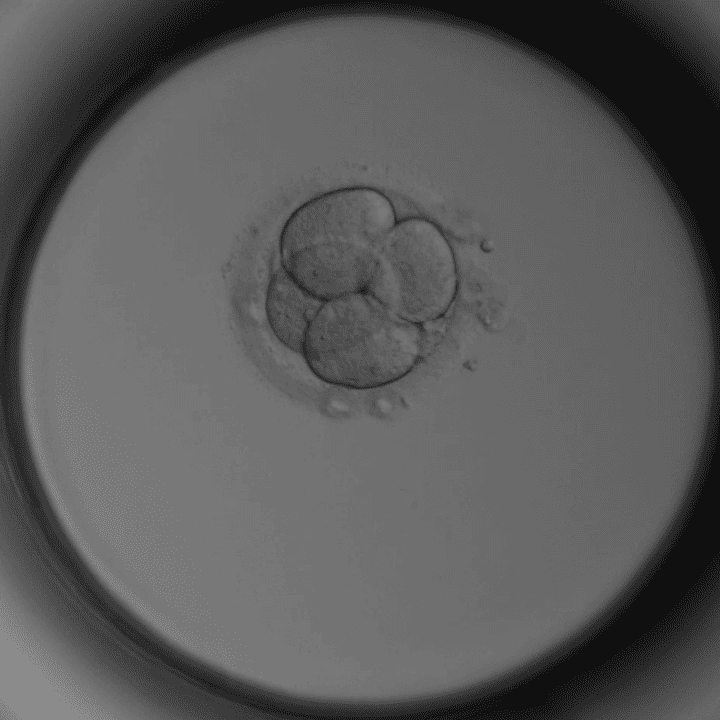

Tag 1 – PN-Stadium

Zwei Vorkerne sichtbar – erfolgreiche Befruchtung.

Tag 1–2 – 2 Zellen

Erste Zellteilung hat stattgefunden.

Tag 2 – 4 Zellen

Gleichmäßige Zellen – gutes Zeichen.

Tag 3 – 8 Zellen

Kompaktierung beginnt.

Tag 4 – Morula

Zellen verschmolzen, Blastozystenreifung beginnt.

Tag 5 – Blastozyste

100+ Zellen. Optimaler Zeitpunkt für Transfer oder Einfrieren.

Mikroskopaufnahmen aus unserem Embryologie-Labor in Thalheim bei Wels (Timelapse-Inkubator).

Nur die besten Embryonen werden transferiert oder eingefroren. Manche Embryonen entwickeln sich nicht weiter – das ist biologisch normal.

Dieser Artikel wurde von Dr. Roman Pavlik, Facharzt für Gynäkologie und Reproduktionsmedizin und ärztlicher Leiter der Kinderwunschklinik Dr. Pavlik in Thalheim bei Wels, verfasst. Die Embryo-Mikroskopbilder stammen aus unserem eigenen Labor – sie zeigen echte Entwicklungsstadien aus der täglichen Arbeit unseres Embryologie-Teams.